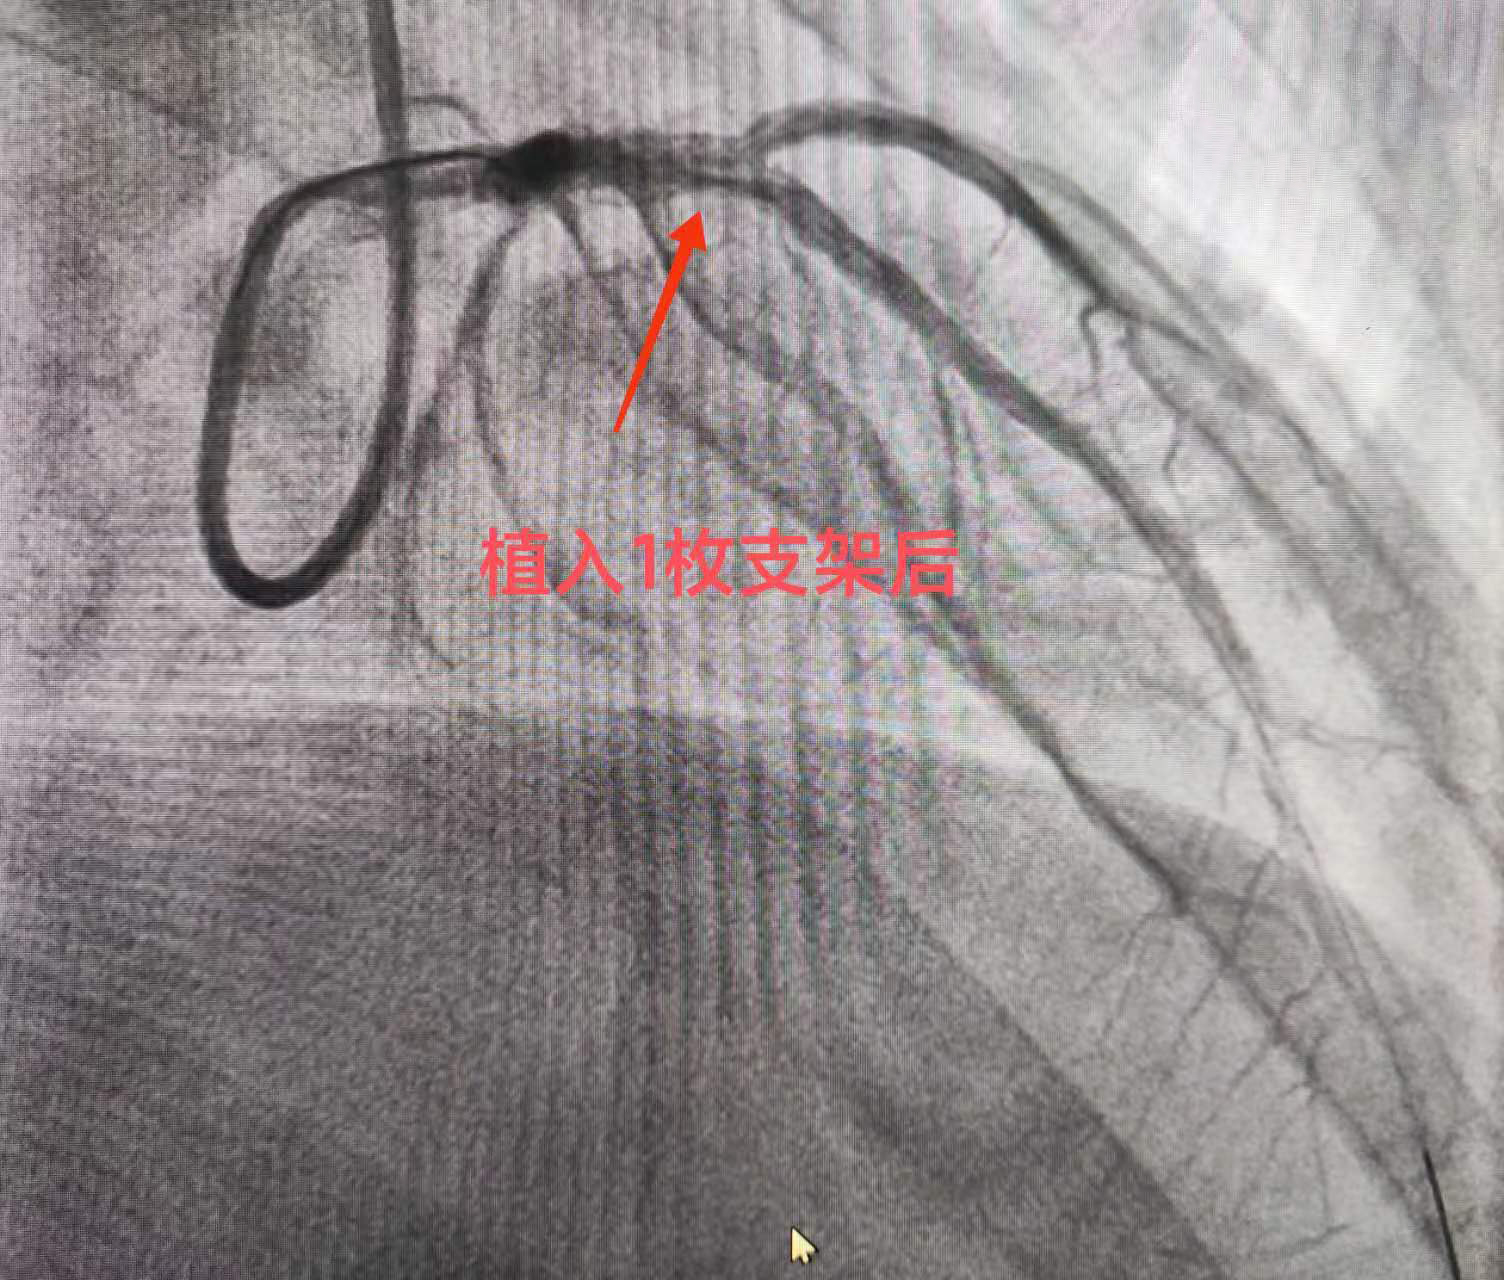

导管室内,秉承患者生命至上的原则,医院迅速安排当日前来坐诊的河北以岭医院心血管病科洪衡主任医师(河北省急救医学会胸痛专业委员会主委)及介入团队为其行冠脉造影。造影显示:前降支——开口至近段30-90%节段性狭窄。在取得家属的同意下行冠脉支架植入术,于前降支植入一枚支架。术毕,患者胸痛明显缓解,安返病房,给予密切监护。